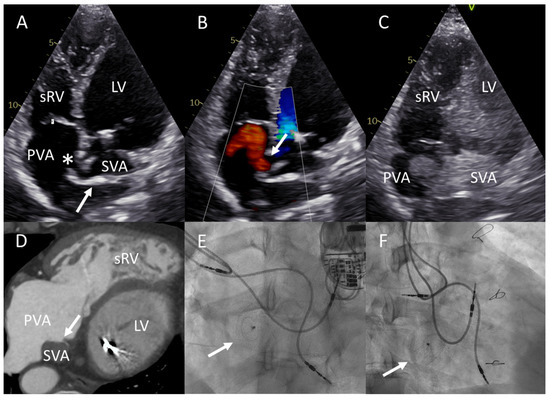

2.3. Patient C